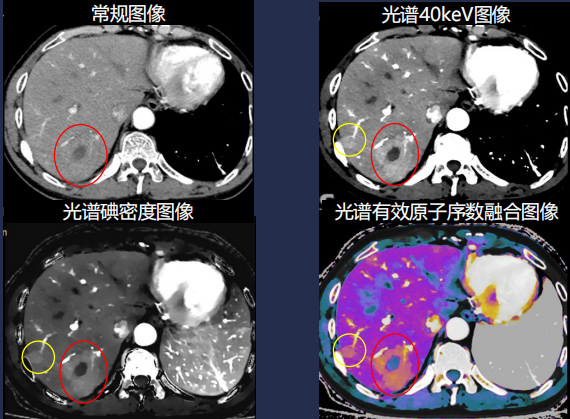

肿瘤诊疗一体化 让肿瘤无处遁形

皓克CT的多参数低keV、有效原子序数、碘含量、虚拟平扫等多种参数可 对全身各部位肿瘤进行多角度分析,突破传统CT的等密度病灶局限,超 早期即可发现肿瘤病变,并可对其进行准确定量、定性分析,辅助肿瘤的 准确分期、分级,协助临床制定治疗方案。肿瘤克星(肿瘤早发现;肿瘤精准分期;肿瘤疗效评估)